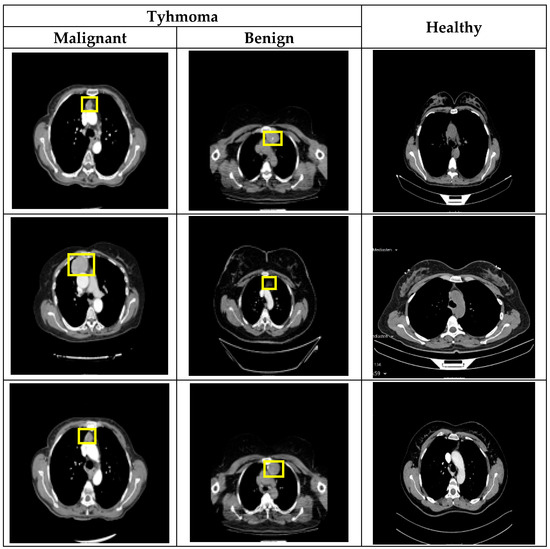

In the proposed preprocessing step, the first stage involves cropping the image based on the possible anatomical location where the tumor (thymoma) is commonly observed. The thymoma tumor typically occurs in the mediastinal region, that is, between the lungs within the thoracic cavity. Based on this, as shown in Figure 2a, the CT image is divided into a 3 × 3 grid. As a result of this division, the images in the first and second rows of the second column are cropped and selected for analysis. This approach directly focuses the model’s attention on areas where tumor formation is most likely, thereby increasing data efficiency. In this way, the limited data is utilized in the most efficient manner, and the diagnostic sensitivity of the model is also significantly improved. The second step in preprocessing involves reducing the number of CT slices (Figure 2b). Here, direct resizing was avoided because it could result in the loss of the limited number of tumor-containing slices. Additionally, since there is generally a high degree of similarity between slices, anomalies such as tumors can often be detected from the differences between them. Therefore, to reduce the data without losing details between slices, three consecutive grayscale slices were combined to create a three-channel (RGB-like) image. In this way, the number of slices is reduced without data loss, while also obtaining an input size suitable for the pre-trained VGG network architecture.

3.5.3. Preprocessing Stage Analysis

To evaluate the effectiveness of using cropped images in the preprocessing step, the proposed model was tested in an ablation analysis alongside various DL-based models. In this analysis, experimental studies were conducted separately for single-channel and RGB inputs, and a comparison was made with the use of entire slice images to determine the impact of cropping. The F1 score values resulting from these experiments are presented in Table 5. Table 5 presents the F1 scores achieved by different models—InceptionResNetV2, DenseNet121, InceptionV3, VGG16, and the proposed model—under two preprocessing scenarios: entire slice image and cropped image, each evaluated with both single-channel and RGB formats. The results clearly show that the proposed model consistently outperforms the others across all preprocessing types. Notably, it achieves the highest F1 score (80.99%) when using cropped images in RGB format, confirming the effectiveness of both the cropping strategy and color information in enhancing classification performance. Comparatively, all models show improved performance when using cropped images versus entire slices, especially with RGB inputs—e.g., VGG16 improves from 74.53% to 75.57%, and InceptionResNetV2 from 72.30% to 76.83%. This trend highlights the advantage of focusing on the region of interest in medical imaging. Overall, these findings validate the preprocessing choice in the proposed model and demonstrate that both cropping and RGB formatting contribute significantly to improving model performance.